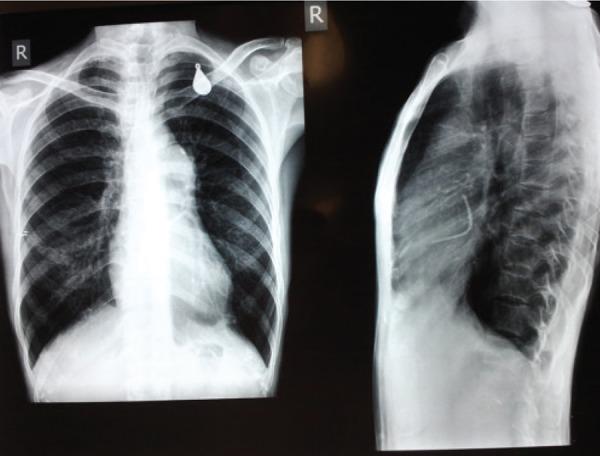

Percutaneous pulmonary balloon valvuloplasty as a procedure of choice in adults has been established since the last three decades. Even though the complications are rare, they are scarcely reported in the literature. We report such a case in an adult female patient of severe pulmonary valular stenosis in whom, entrapped catheter across the fossa ovalis was noted in chest x-ray and echocardiogram following unsuccessful percutaneous pulmonary balloon valvuloplasty. Our case emphasizes this rare complication and its successful surgical outcome.